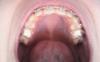

Давно я здесь не писала:( забыла про Вас..но читаю почти всегда... сегодня орт сказала, что все очень хорошо и месяца через 2-3 будем снимать.. это конечно хорошая новость, но я что то сомневаюсь. Может я просто уже придираюсь? Поэтому обращаюсь к Вам...

img_20140218_165408.jpg

img_20140218_165536.jpg

img_20140218_165725.jpg

img_20140218_165831.jpg